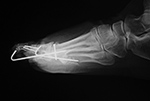

71 year-old woman with surgery for recurrent hammertoes. There are Smart Toe implants fusing the right second and third interphalangeal joints. A small cortical screw goes through the second metatarsal neck, and there are K wires in the fourth and fifth toes. |